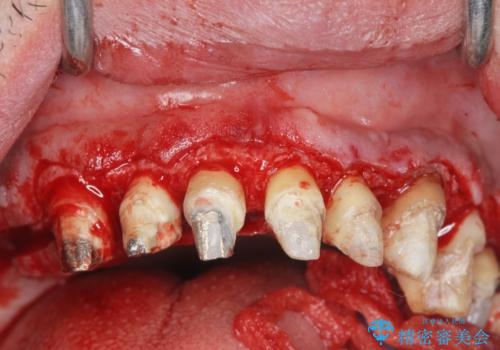

歯周組織検査を行うと歯ぐきからは容易に出血し、X線検査より歯とセラミッククラウンの適合が悪い(ピッタリと合っていない)状態が示唆され、歯ぐきの炎症を惹起している状態でした。

セラミッククラウンを除去し仮歯を装着し、歯周外科手術を行い歯ぐきの状態を改善したのち、適合の良いセラミッククラウンを再作製をする治療計画としました。